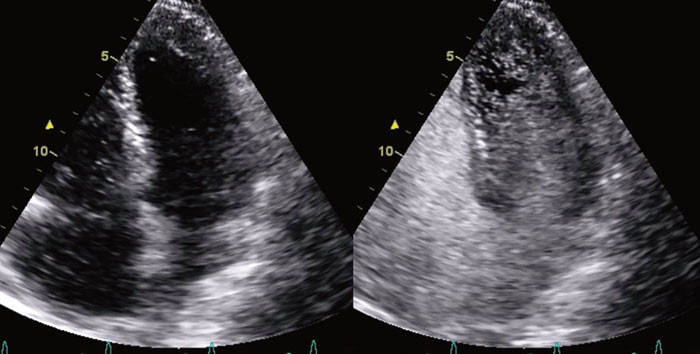

I en noe uortodoks projeksjon fremkom det at trikuspidalinsuffiensen var stor (grad 3 – 4/4). Trikuspidalklaffens seil var fortykket, korte og lite mobile. Klaffeseilene sto i halvåpen posisjon i systolen når de skulle være lukket. De påviste forandringene i trikuspidalapparatet ga mistanke om karsinoid hjertesykdom. Ved å plassere ultralydhodet under kostalbuen kunne leveren visualiseres. Leveren var inhomogen med multiple ekkotette lesjoner, slik at mistanken om karsinoid sykdom ble ytterligere forsterket (fig 3).

Karsinoide avleiringer på trikuspidalseilene hadde medført progredierende trikuspidalinsuffisiens. Dette førte videre til økt trykk i atriet med stor shunting av blod gjennom det åpenstående foramen ovale. Pulmonalklaffen, aortaklaffen og mitralklaffen hadde kun mindre insuffisienser, uten tegn til karsinoide forandringer. Karsinoide tumorer kan produsere en rekke ulike substanser, bl.a. serotonin som er sentralt i patogenesen ved karsinoid hjertesykdom. Serotonin aktiverer myofibroblaster som lager karakteristiske kollagenavleiringer i hjertets klaffeapparat (5, 6). Da serotonin inaktiveres i pulmonalkretsløpet, rammes hyppigst det høyresidige klaffeapparatet, og trikuspidalklaffen affiseres hyppigere enn pulmonalklaffen. Affeksjon av det venstresidige klaffeapparatet er mer sjeldent, og er assosiert med åpent foramen ovale, bronkial karsinoid eller utbredt metastasering (6, 7).